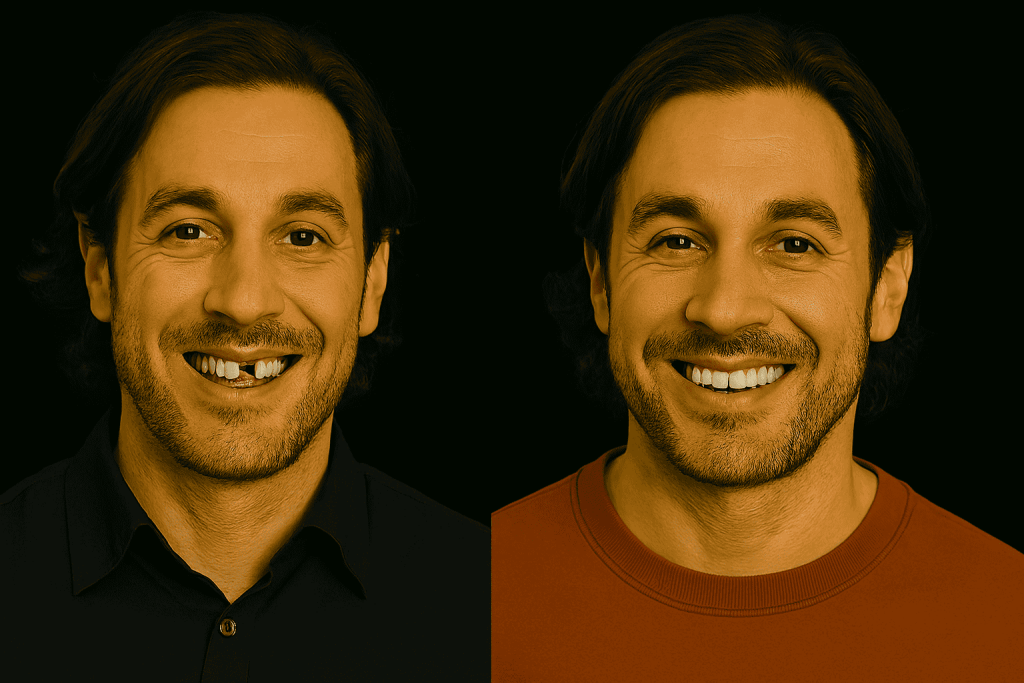

Prima e dopo impianti dentali in Turchia

Le foto prima e dopo mostrano in modo concreto le trasformazioni possibili e completano le recensioni sugli impianti dentali in Turchia. Questi interventi offrono una soluzione affidabile per sostituire i denti mancanti, migliorare l’estetica del sorriso e ritrovare una masticazione confortevole e naturale.

L’evoluzione dei risultati conferma l’affidabilità di questo trattamento, come dimostrano le numerose recensioni sugli impianti dentali in Turchia. I pazienti sottolineano sia il miglioramento estetico, sia la solidità ritrovata e il netto aumento della qualità di vita dopo l’intervento.